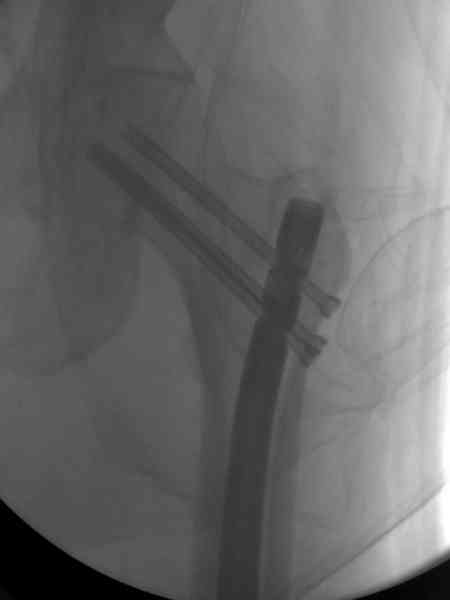

В первый же день произведено антеградное штифтованием DePuy Trochanteric Nail.

На второй день (7) обнаружен пропущенный перелом,

сделаны Компьютерная Томограмма

и проведены шурурпы через и спереди штифта без удаления.